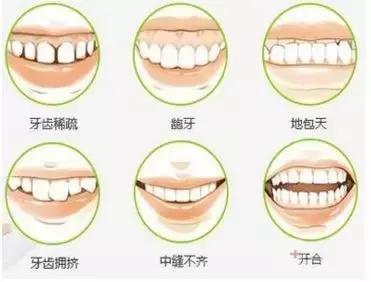

所以首先,大多数人戴牙套的动机:牙齿不好看。这是最直观的一点,你的牙齿是否整齐、漂亮,是会直接影响到颜值的高低。另外,牙齿问题还可能会影响脸型,特别是侧貌,例如嘴突、地包天等。

如果你的牙齿符合上面六种情况中的一种,那么就可以考虑通过牙齿矫正来解决。